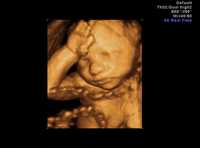

Ampliar la imagen Imagen tridimensional de un feto de 23 semanas Imagen tridimensional de un feto de 23 semanas Foto: Reuters

Una de las influencias más fuertes en el debate ha sido la publicación de innovadoras imágenes tridimensionales en movimiento producidas por el profesor Stuart Campbell, especialista en obstetricia y pionero en diagnóstico fetal por ultrasonido.

Sus videos y fotografías muestran claramente fetos de 16 semanas chupándose el dedo, bostezando y manifestando conductas que sugieren que en esta etapa están mucho más desarrollados de lo que se pensaba.

“Me sorprendió lo complejo que es el feto”, aseguró Campbell. “El patrón de conducta de sus brazos y manos muestra que sólo está adquiriendo conciencia espacial y aprendiendo sobre su entorno.

“Por supuesto que no creo que esto ocurra a nivel cerebral –no es un ser inteligente en ese momento–, pero sus patrones reflejos de conducta se están preparando para una vida futura”, añadió.